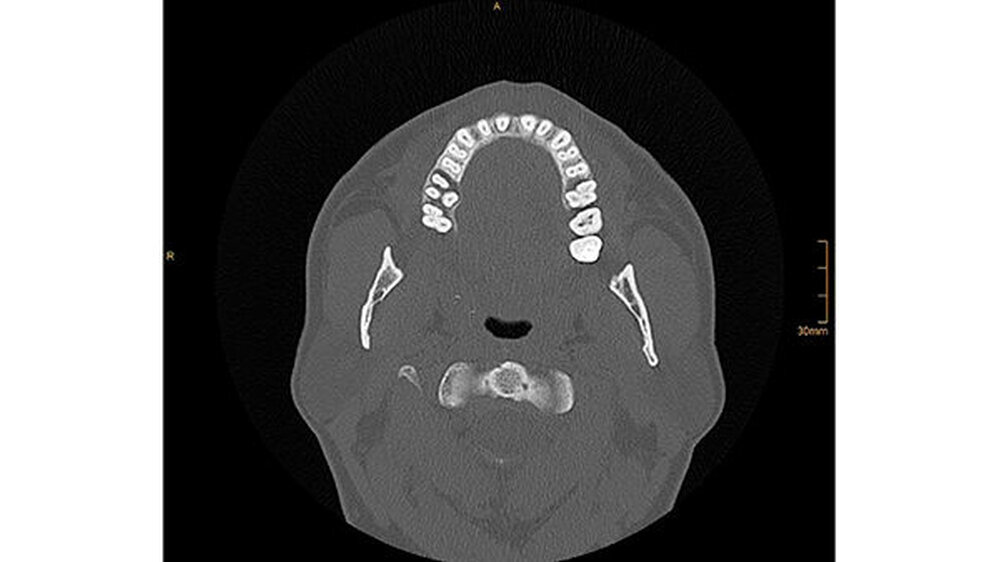

Die CT-Aufnahmen zeigen eine deutliche bis zum Orbitaboden heranreichende Totalverschattung der rechten Kieferhöhle. In Höhe des Zahns 16 zeigen sich periradikuläre Rarefikationen als Hinweis auf eine aggressive lokale Parodontitis.